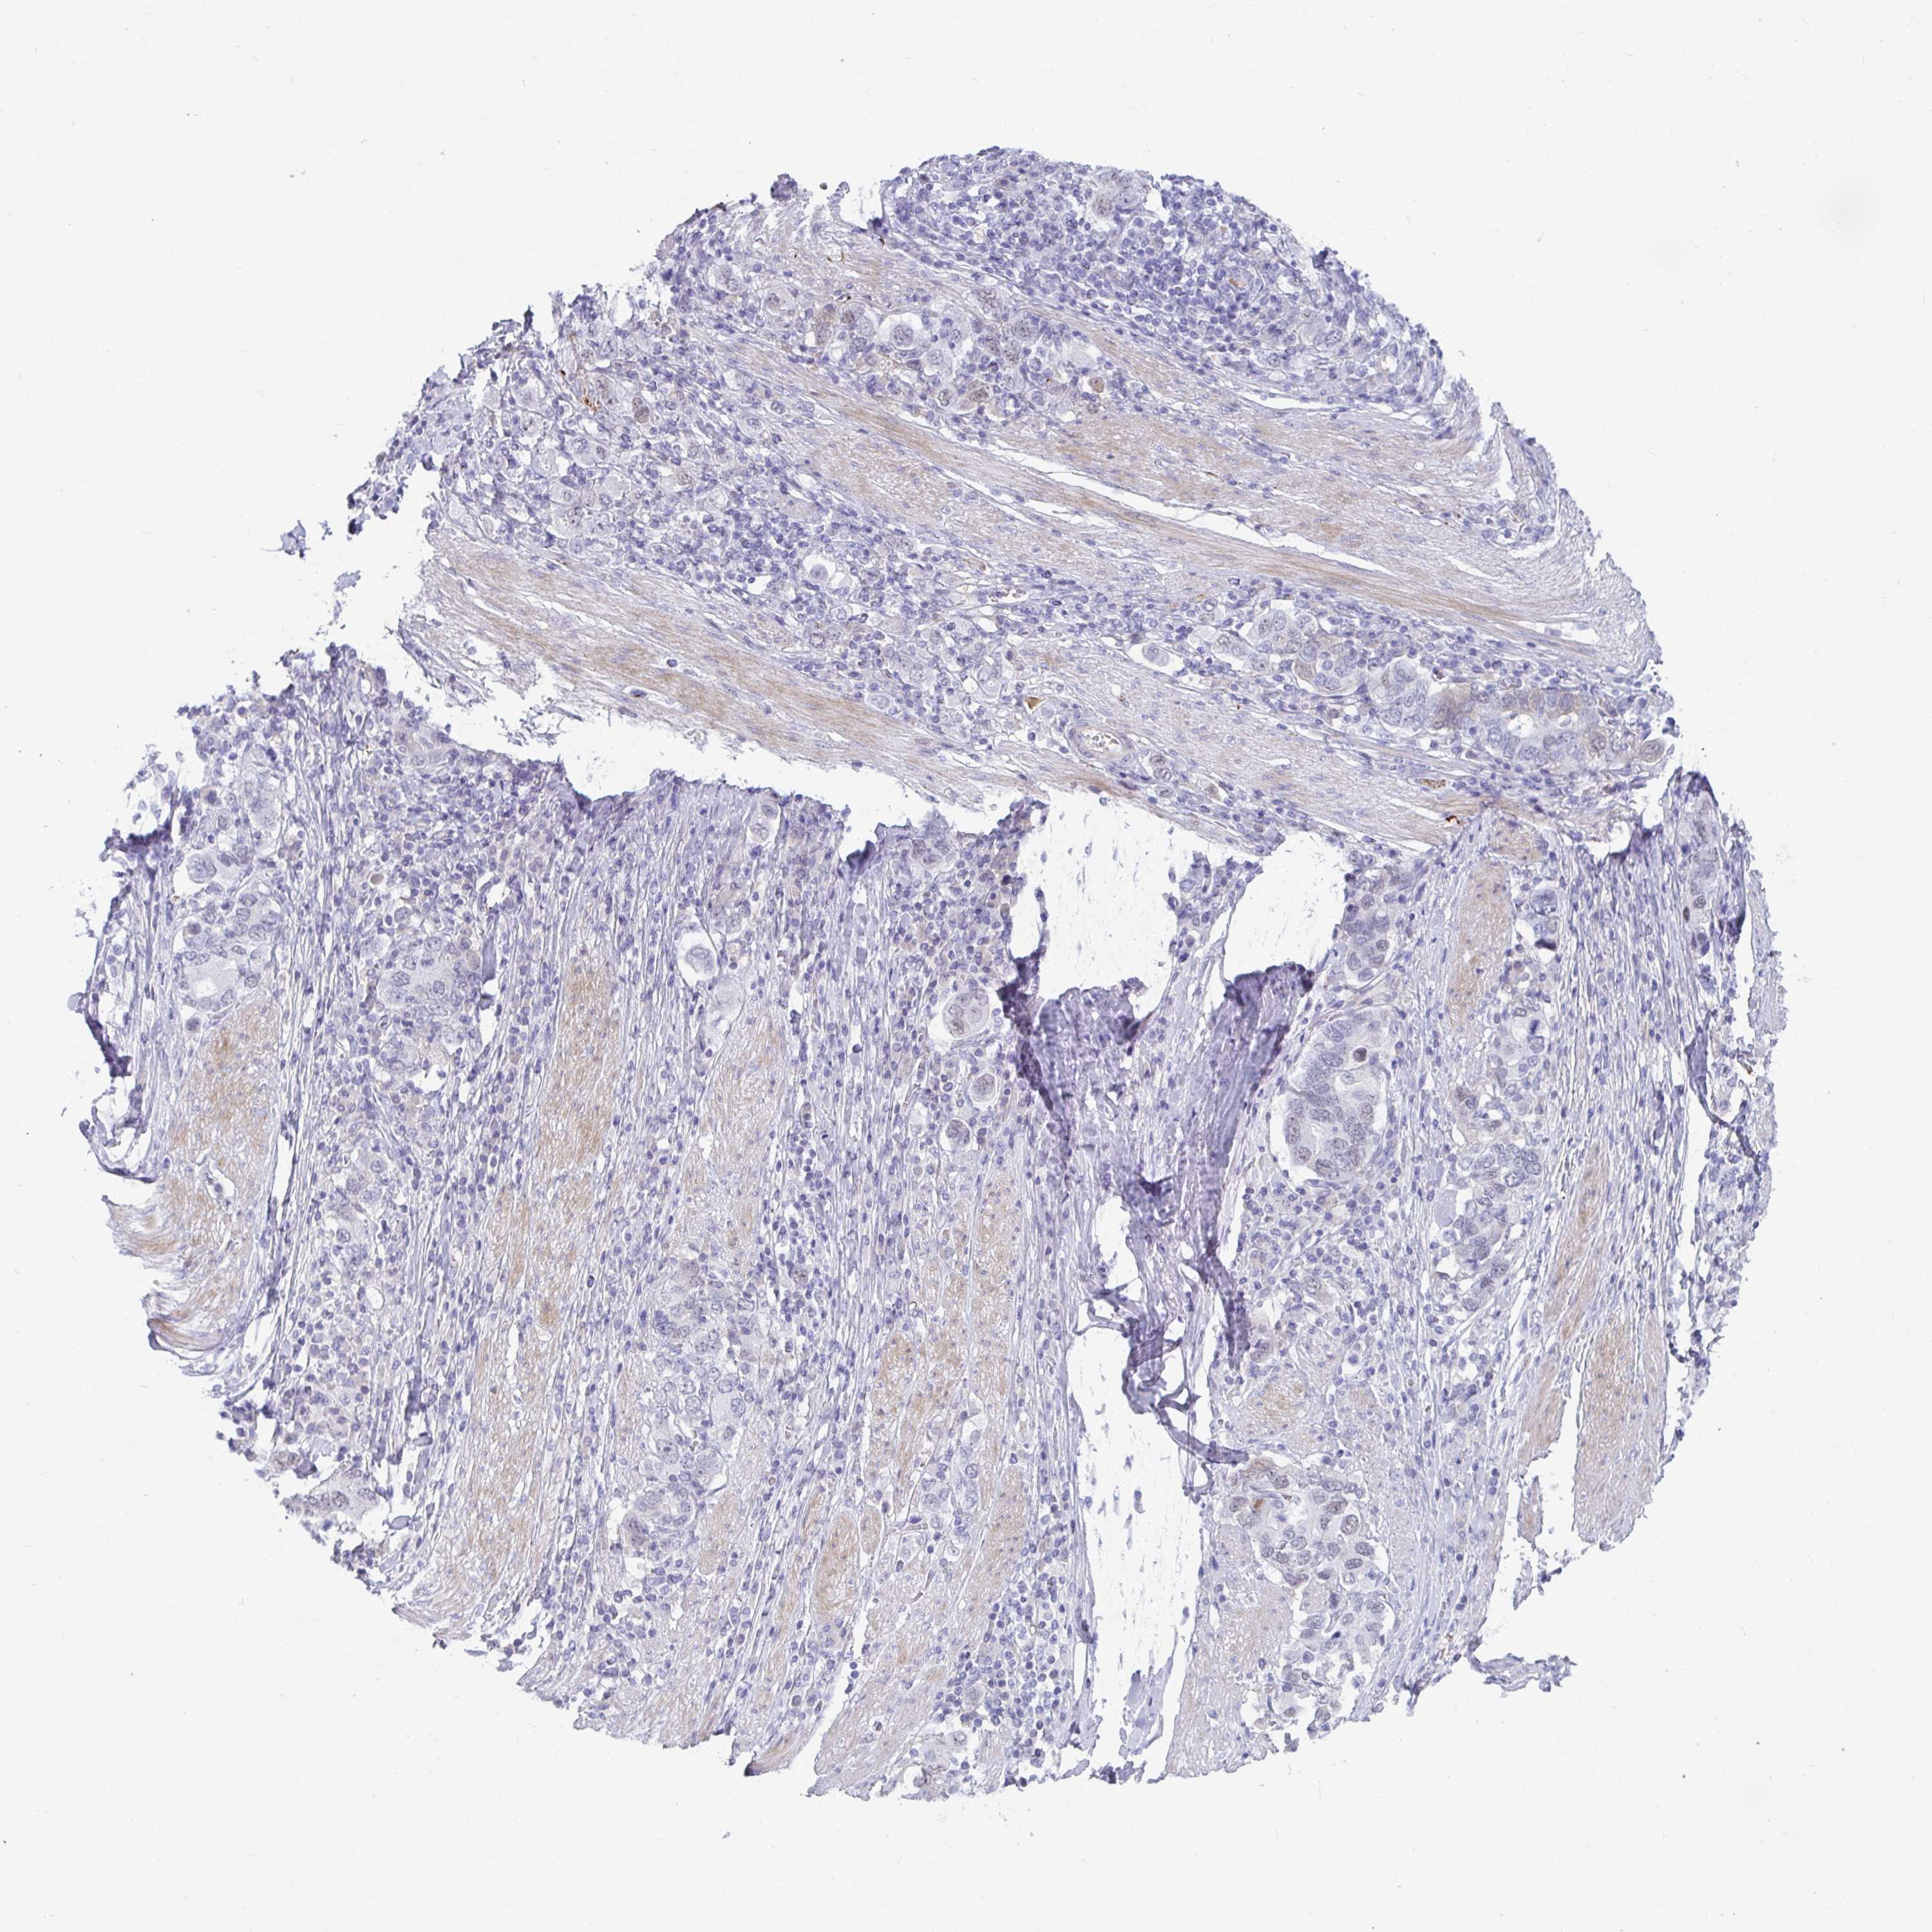

STOMACH CANCER - Protein expressioni

A mouse-over function shows sample information and annotation data. Click on an image to view it in a full screen mode. Samples can be filtered based on level of antibody staining by selecting one or several of the following categories: high, medium, low and not detected. The assay and annotation is described here.

Note that samples used for immunohistochemistry by the Human Protein Atlas do not correspond to samples in the TCGA dataset.

Antibody stainingi

Antibody staining in the annotated cell types in the current human tissue is reported as not detected, low, medium, or high, based on conventional immunohistochemistry profiling in selected tissues. This score is based on the combination of the staining intensity and fraction of stained cells.

Each image is clickable and will lead to virtual microscopy that enables deeper exploration of all samples and also displays staining intensity scores, fraction scores and subcellular localization as well as patient and tissue information for each sample.

Antibody CAB034368

Staining

High

Medium

Low

Not detected

Intensity

Strong

Moderate

Weak

Negative

Quantity

>75%

75%-25%

<25%

None

Location

Nuclear

Cytoplasmic/membranous

Cytoplasmic/membranous,nuclear

Adenocarcinoma, NOS